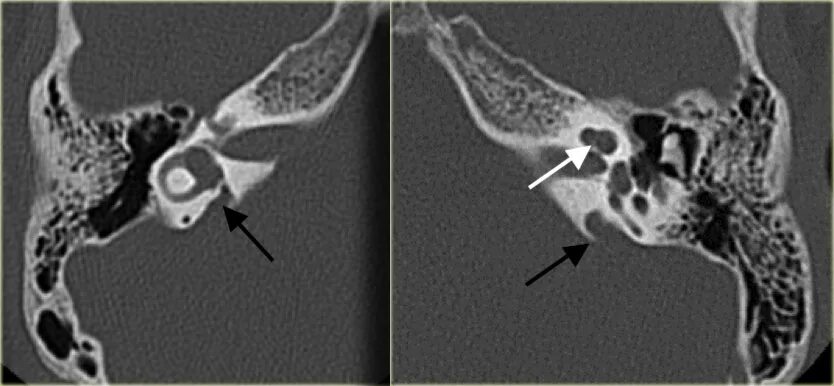

Кохлеарный отосклероз